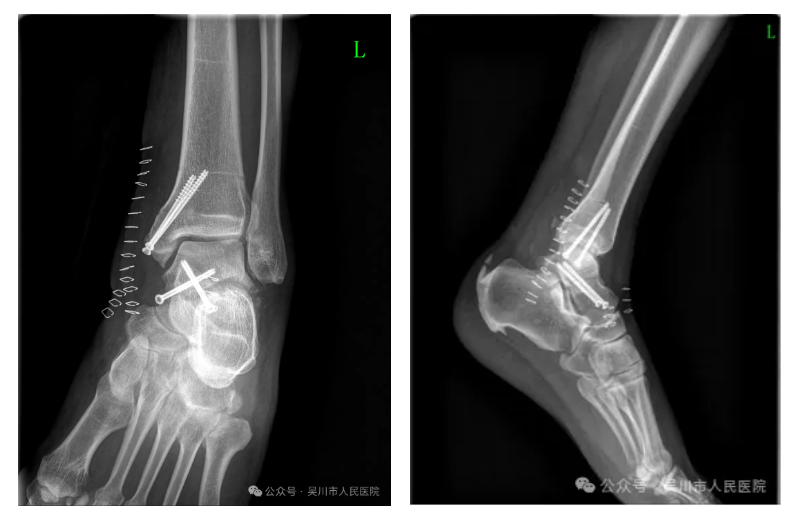

患者一周前因意外导致左踝部严重受伤。送入我院时,患者的左踝已严重肿胀变形。CT提示左侧内踝骨折、距骨粉碎性骨折合并脱位,关节面损伤,脆弱的血管神经束受到碎裂骨块的压迫。

面对复杂病情,在广东省中医院陈海云教授的指导下,我院骨外科一区联合医学影像科,利用三维重建技术进行多次术前模拟推演,最终确定了“有限切开结合微创内固定”的方案。

手术过程中,手术团队运用直径仅2毫米的导针,在狭窄的骨缝间小心翼翼地穿行,将塌陷的关节面逐一复位,再用中空螺钉稳稳固定核心结构,全程借助术中透视技术,确保每一枚螺钉的位置、深度都恰到好处,既实现了牢固固定,又完美避开了周围的血管神经。历时3小时,成功完成了这场高难度的“骨骼修复工程”。